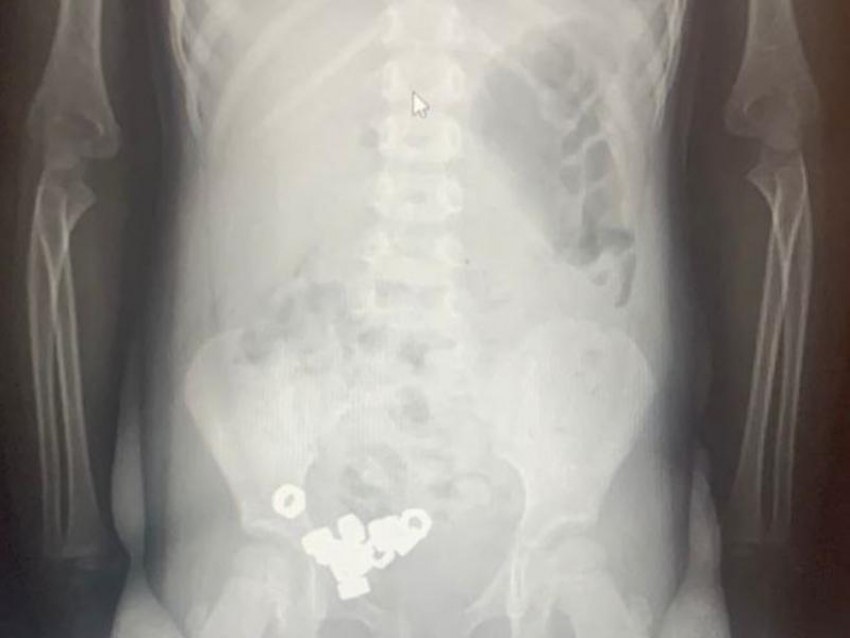

Симптомов у маленького пациента не было, но рентген показал 16 маленьких гаек в желудочно-кишечном тракте. Из-за высокого риска осложнений ребенка госпитализировали, чтобы наблюдать за его состоянием.